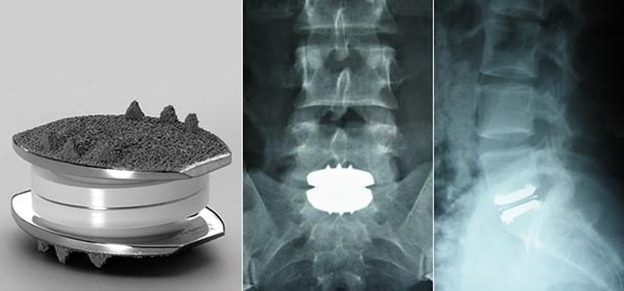

Partial or total joint replacement surgery (arthroplasty) removes the damaged joint surfaces and replaces them with plastic or metal parts.1,33 As shown by Figures 12 & 13, this can occur in the knee, hip, fingers, wrists, shoulders, etc.35-37 Figures 14 & 15 depict the spine equivalent, which are artificial disc replacements.38,39 Partial replacement will only remove some parts of the joint and total replacement will replace the entire joint with an artificial joint. The artificial joints can be composed of metal alloys (i.e. titanium, cobalt chrome, or stainless steel), polyethylene, or ceramic.40 Potential complications of arthroplasty include blood clots, internal infections, nerve damage, blood vessel damage, scar tissue, or reduced range of motion. The implant may also experience loosening or wear down over time, which may make it unsuitable for younger patients.37

Figure 15 X-ray of an artificial lumbar disc replacement.39

This image shows an artificial lumbar disc replacement and an X-ray of the disc replacement once implanted into the spine.